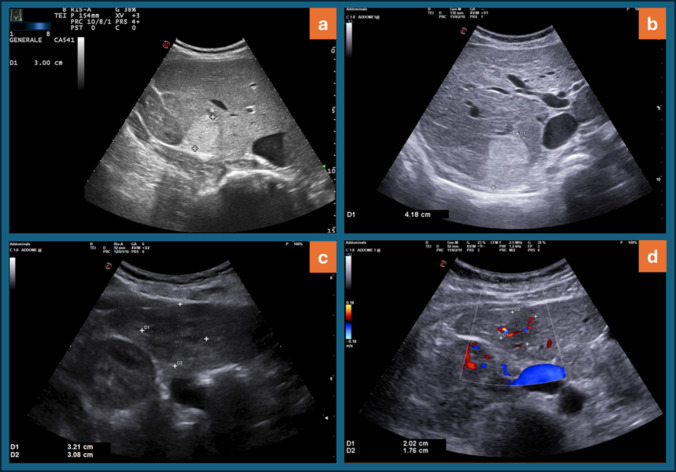

Purpose: To examine the natural history of focal nodular hyperplasia (FNH) lesions through long-term ultrasound (US) follow-up and assess the relationship between clinical characteristics and size changes.

Methods: We retrospectively enrolled 55 patients diagnosed with FNH who were followed with ultrasound for at least 24 months. A total of 94 FNH nodules were included in the final analysis. A significant change in size was defined as an increase or decrease of 0.5 cm or more, and nodules were classified as increased, decreased or stable. Additionally, we analyzed the association between clinical data and changes in nodule size.

Results: The mean follow-up duration between the initial US examination at diagnosis and the last available examination was 58.3 ± 33.5 months (range: 24.2-186.6). The majority of nodules remained stable (47.9%) or decreased in size (35.1%), while a small proportion of nodules disappeared (11.7%) and only 7.3% showed an increase in size. No significant association was found between size variation and factors such as oral contraceptive use, pregnancy, BMI or follow-up duration.

Conclusion: Changes in the size of FNHs during follow-up are relatively common, with most lesions remaining stable or undergoing regression or disappearance over time. These size variations do not appear to be influenced by hormonal factors or other clinical characteristics.